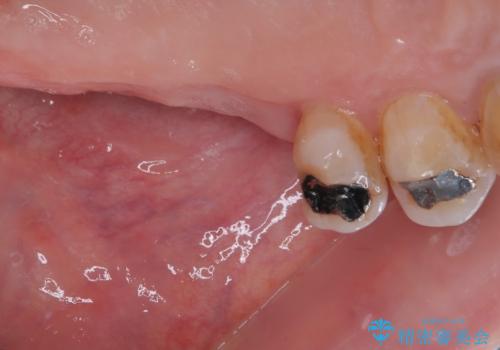

骨量の少ない上顎大臼歯 骨補填材を用いない短期間インプラント治療

- 近医にて入れ歯が合わないためインプラント治療を希望したものの、治療期間が長く大変と聞き、当院を受診された患者様です。

レントゲンから分かるとおり、インプラント埋入に必要な骨の高さが著しく不足している状態でした。

数年前まで当院でも行われていた従来の手法では、骨補填材による上顎洞底の挙上を行い、インプラント埋入に半年以上の期間を必要とするものでした。

しかしながら、ここ数年で流通してきたデンサーバーというドリルと、エキストラワイドショートインプラントの併用により、骨補填材による上顎洞底の挙上なしに埋入が行えるようになりました。

元々の骨量が少なく、通常よりは待機期間が長くなりますが、数ヶ月程度で補綴治療まで行うことができるため、こちらの手法でインプラント補綴治療を行うこととしました。